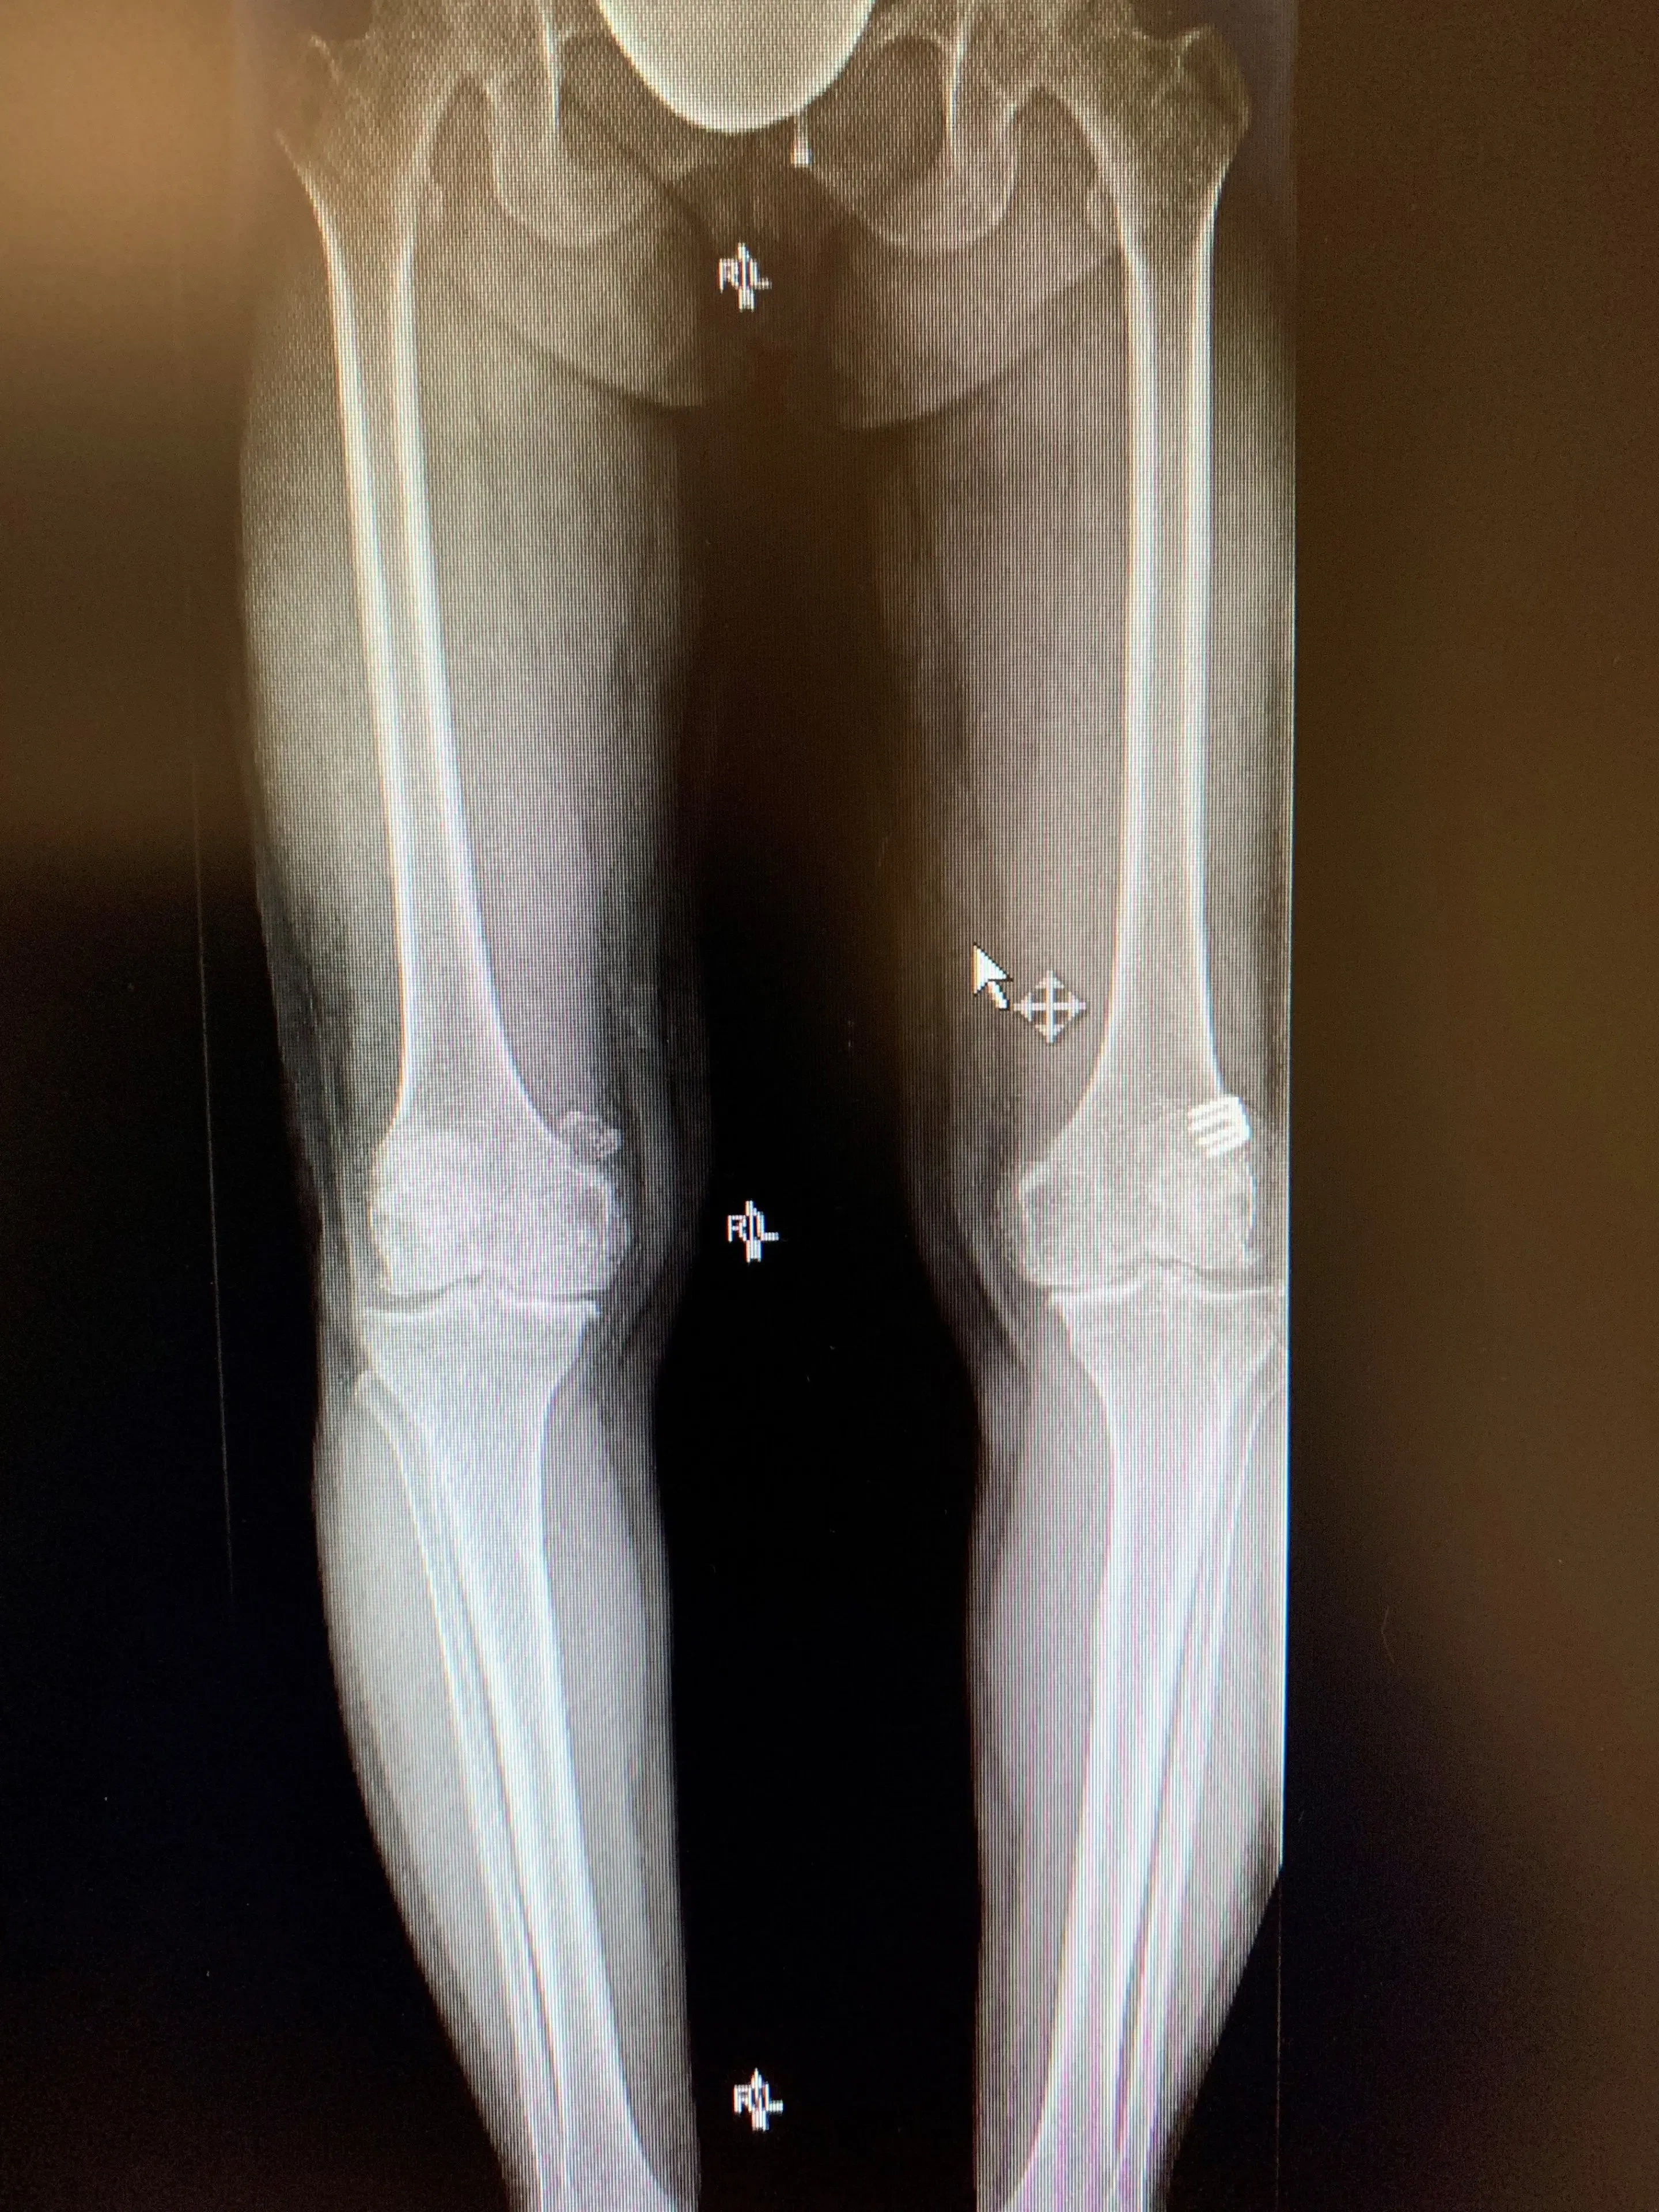

Her X-rays revealed bilateral varus osteoarthritis of approximately equal severity in each knee.

Pre-op

Simultaneous bilateral knee replacement in a 54-year-old female.